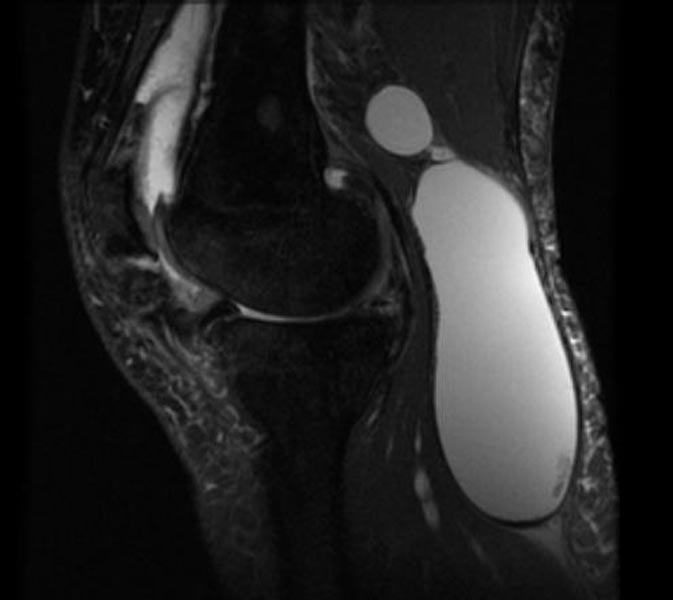

Фото и диагностика кисты Бейкера